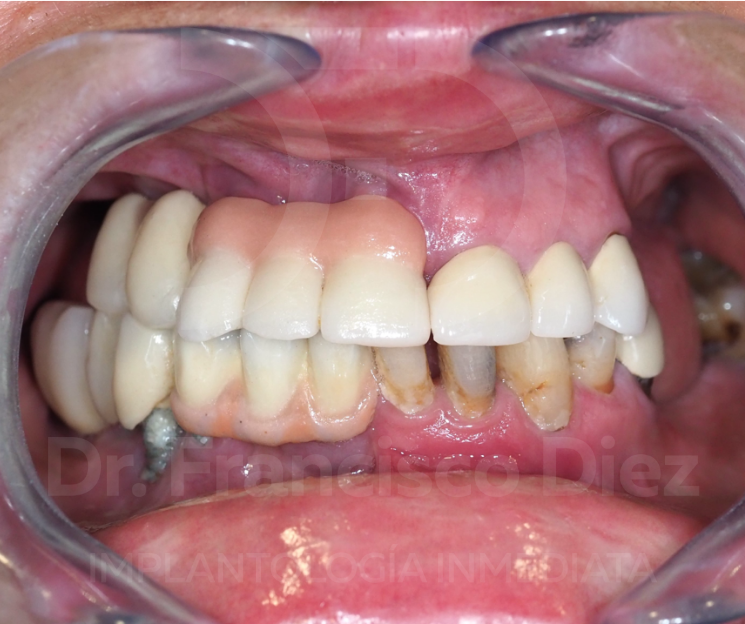

Recibimos con frecuencia a pacientes de avanzada edad que acuden con un problema común, pero devastador: molestias en la boca que les imposibilitan comer bien, alteran su vida cotidiana y afectan su estado general. No se trata solo de una dificultad funcional. Detrás de cada mueca de dolor hay también un golpe al estado de ánimo. Muchos de ellos han dejado de sonreír por el aspecto negativo de sus dientes, avergonzados ante su propia imagen.

Lamentablemente, este sufrimiento suele tener un origen evitable: un mal diagnóstico y un tratamiento erróneo. En lugar de solucionar el problema, muchos pacientes reciben rehabilitaciones bucales que, con el paso de los años, derivan en múltiples problemas infecciosos y estéticos. Lejos de mejorar, su situación se agrava. Y las consecuencias de una mala elección clínica no son solo estéticas: afectan la salud oral, la salud general y la psicológica. Al ver un panorama desolador, sin esperanza de mejora, muchos terminan abandonándose hasta que la situación se vuelve insostenible.

Veremos el caso clínico de un paciente de avanzada edad que llegó con estos problemas: no podía comer, ni sonreír, tras un mal diagnóstico y tratamiento erróneo.

Un factor crítico que agrava este escenario es la enfermedad periodontal. Las personas con predisposición a esta condición suelen terminar desarrollando periimplantitis cuando reciben implantes convencionales. El resultado es un empeoramiento muy significativo de su salud bucal. Intentar volver a colocar el mismo tipo de implante sería un gravísimo error, que conllevaría múltiples intervenciones, largas esperas y, a menudo, un resultado dudoso.